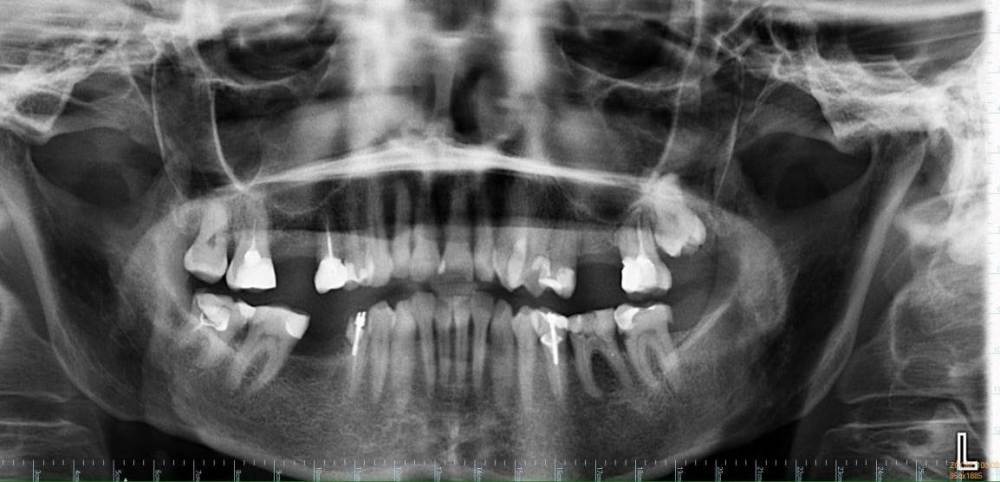

ElenaN Опубликовано 27 апреля, 2021 Поделиться Опубликовано 27 апреля, 2021 (изменено) Есть ли отверстие (перфорация) между гайморовой пазухой и ротовой полостью СПРАВА вверху после удаления 6 верхнего зуба?? Как на ваш взгляд? Одни врачи срочно посылают на операцию на основании только этого снимка, другие говорят, что дырки нет, пазуха спокойна и не нужно ничего трогать, чтобы не было хуже. Посмотрите, пожалуйста, что за ситуацию вы видите? Чтобы не перепутать с левой (здоровой) стороной - под больным местом снизу зуба тоже нет. Проблема - СПРАВА (около левой стороны написано "L"). 16.10.2020 удалили 6-ку сверху справа, боль совсем не проходит уже 7 месяцев. Только на 4-м по счёту панорамном снимке от 16.04.2021 (прикреплён) уже в другой клинике нашли перфорацию гайморовой пазухи при удалении зуба (There was an OAC present intraorally). Рекомендация - операция как можно быстрее, чтобы закрыть отверстие. Показать мне на снимке, где именно нашли отверстие, доктора отказались. Обратилась к другому врачу - он никакого прободения не видит. Говорит, что после операции может быть только хуже. Нужно искать другую причину боли. Пожалуйста, посмотрите. Мучаюсь от боли уже 7 месяцев. На вторую врачебную ошибку не готова. Не в России, из-за карантина не могу добраться до специалистов. Буду благодарна за любые версии. Других признаков сообщения с пазухой нет: могу надуть щёки, из носа ничего не бежит, пища в нос не попадает, плохо не пахнет, запахи все чувствую, как раньше, голос не менялся и т.п. Боль на месте удаления, концентрируется вдоль пятого зуба уходит вверх, от 3 до 10 по шкале до 10. Боль постоянная, фоновая, резкой, чтоб подскакивала, не бывает. Если удаётся уснуть - не просыпаюсь. Десна над местом удаления около 5 чувствительна, кость над местом удаления реагирует на горячее больше, на холодное меньше. К щеке прикасаться неприятно, в пазухе иногда свербит. Что-то в этом месте неправильно и нехорошо. За 7 месяцев потихоньку схожу с ума. Но есть ли дырка? Нужна ли операция? И насколько срочно? Изменено 27 апреля, 2021 пользователем ElenaN опечатка Ссылка на комментарий

Irouil Опубликовано 27 апреля, 2021 Поделиться Опубликовано 27 апреля, 2021 (изменено) По предоставленному снимку точно сказать что-то о наличии перфорации (а если речь идёт о 7 месяцах - стойком соустье) нельзя, но очень вероятно что ее там нет - в месте удаленного зуба все выглядит абсолютно нормально. Да и вся описаная симптоматика на соустье не тянет никак. Есть зубы справа, которые точно нуждаются в санации - это и 5, и 7, и 8 сверху, а так же 5 и 8 снизу. Теоретически, любой из них может быть виновником подобных болей, но самый вероятный кандидат - верхняя 8-ка. Если санация зубов не даст результата - провести диагностику ВНЧС и неврита 2-й ветви тройничного нерва. Очень рекомендую сначала провести КЛКТ исследование челюстей с захватом хотя бы верхнечелюстных пазух P.S. Судя по приведённой формулировке, ОАС Вам диагностировали не по снимку, а при осмотре в полости рта (intraorally), а это - приоритетный источник информации Изменено 27 апреля, 2021 пользователем Irouil 2 Ссылка на комментарий

ElenaN Опубликовано 28 апреля, 2021 Автор Поделиться Опубликовано 28 апреля, 2021 (изменено) 15 часов назад, Irouil сказал: P.S. Судя по приведённой формулировке, ОАС Вам диагностировали не по снимку, а при осмотре в полости рта (intraorally), а это - приоритетный источник информации Спасибо. Там полная формулировка такая: "On examination in the upper right malar region extraorally was some tenderness. There was no swelling but there was some tenderness on the rigth hand side. There was an OAC present intraorally which can be probed 3,5mm and the OAC was visible on the OPG. We have planned for her to have this closed under local anaesthetic". И есть ещё такой более ранний снимок (от марта). @annda Спасибо. Изменено 28 апреля, 2021 пользователем ElenaN Добавила информацию Ссылка на комментарий

Irouil Опубликовано 28 апреля, 2021 Поделиться Опубликовано 28 апреля, 2021 Честно говоря, зондирование на 3.5 мм в глубину мало о чем говорит - в конце концов, зачастую только толщина слизистой полости рта может составлять более 3 мм. По второму снимку, как и по первому, никаких признаков наличия ОАС я не отмечаю Я соглашусь с @anndaчто более всего описанная симптоматика похожа на неврологию, но я сразу хочу предупредить, что многие неврологи могут сначала отправить Вас на санацию полости рта, чтобы исключить влияние любой зубной патологии. 1 Ссылка на комментарий

annda Опубликовано 28 апреля, 2021 Поделиться Опубликовано 28 апреля, 2021 Пародонт у щечномедиального корня 6ки не очень выглядит, трещину бы исключить.Но такой пародонт и от перегрузки может быть.И жалобы на трещину не тянут. 1 Ссылка на комментарий

annda Опубликовано 28 апреля, 2021 Поделиться Опубликовано 28 апреля, 2021 Пардон, 7ка, обсчиталась 1 Ссылка на комментарий

Irouil Опубликовано 28 апреля, 2021 Поделиться Опубликовано 28 апреля, 2021 (изменено) 8 часов назад, ElenaN сказал: @Irouil а что, на первый взгляд, с 8? На что проверять? Надо проверить нет ли там пульпита хронического - по КТ создавалось впечатление что на зубе есть кариозная полость глубокая (по второму снимку она не видна, но очно осмотреть этот зуб все равно стОит - зубные причины описываемых Вами жалоб чаще всего кроются именно в пульпитах) P.S. не по КТ, по ОПТГ, конечно Изменено 28 апреля, 2021 пользователем Irouil 1 Ссылка на комментарий

Bier Опубликовано 28 апреля, 2021 Поделиться Опубликовано 28 апреля, 2021 проверить 8й, 7 и 5 пролечены плохо, как минимум их перелечить. Если 8й проблемный - удалить. 1 Ссылка на комментарий